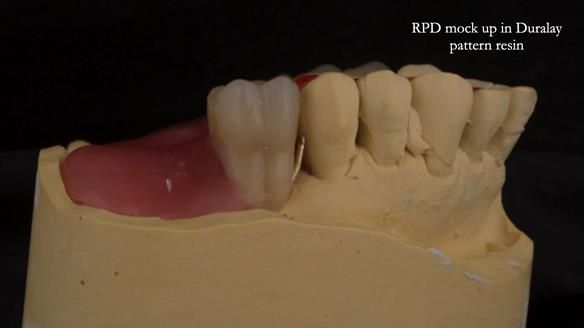

Instead, we made a Scandinavian-style, metal-based lower RPD.

It was made promptly, then relined gradually over the following year

to optimise fit, comfort, and support.

It’s worth saying that the lower denture in this case was made in the early days of Rowan and me using the Scandinavian approach. Rowan cast the metalwork himself for this denture.

Looking back, we would make this denture more hygienic now. The design and finish would be more refined and delicate, particularly when compared with the upper metalwork, which was made later using Chris Hesketh’s chrome work. I will discuss this in detail at the study club.

That said, the lower denture worked beautifully. It did exactly what it was meant to do, even though, by today’s standards, it looks a little agricultural.